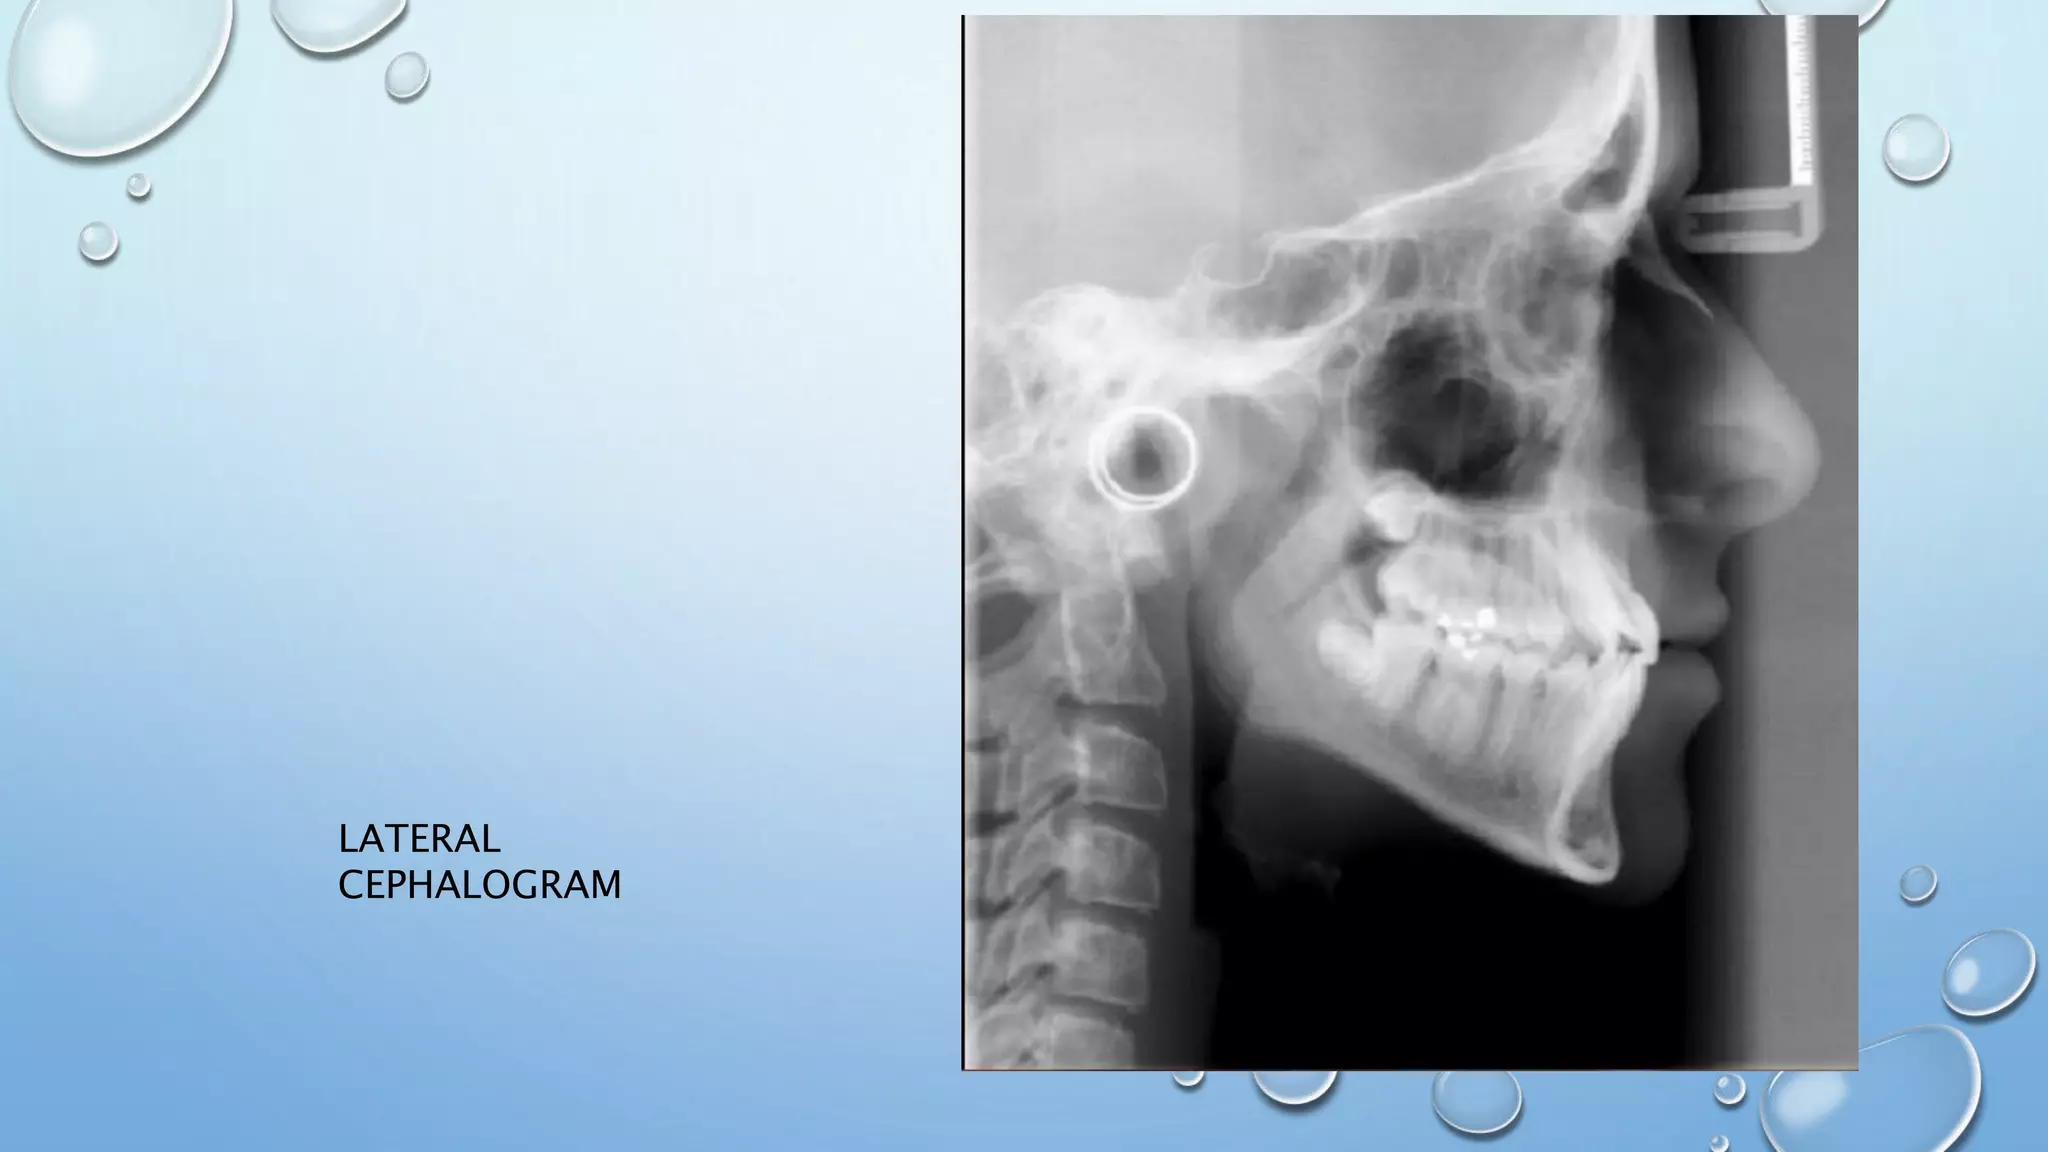

LATERAL

CEPHALOGRAM